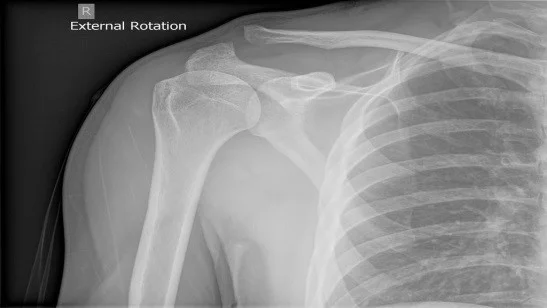

A 19 year-old male presents to the emergency department with a complaint of right shoulder pain. He was tackled from behind in a rugby game three days prior to presentation and has been experiencing pain over the anterior aspect of his right shoulder since that time. Physical exam is notable for tenderness over the right acromioclavicular (AC) joint and pain with both active and passive range of motion of the right shoulder. X-rays (Figure 1) show “no obvious fracture or subluxation.” However, based on your exam and clinical suspicion, closer inspection reveals abnormal alignment between the clavicle and the acromion consistent with AC joint injury.

Figure 1

Figure 1: Case courtesy of Dr Henry Knipe, <a href="https://radiopaedia.org/">Radiopaedia.org</a>. From the case <a href="https://radiopaedia.org/cases/30774">rID: 30774</a>